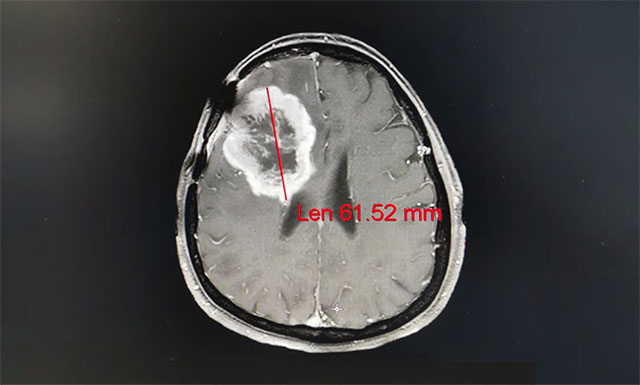

▲ 患者脑胶质瘤复发,症状严重不能自理

完善其各项检查,王晓东主任根据姚女士的临床资料、病理诊断和影像结果,确定患者满足放疗条件,并制定了完善周密的放疗计划。之后患者进行了一个疗程(30次)的放射治疗,放疗期间未见明显不良反应,经过放射治疗,姚女士的病灶由原来的61.52mm缩小到50.33mm;其头痛、恶心症状明显改善,大小便也恢复正常,走路不稳的症状也得到了缓解。

▲ 经过放射治疗患者病灶变小,其症状明显改善